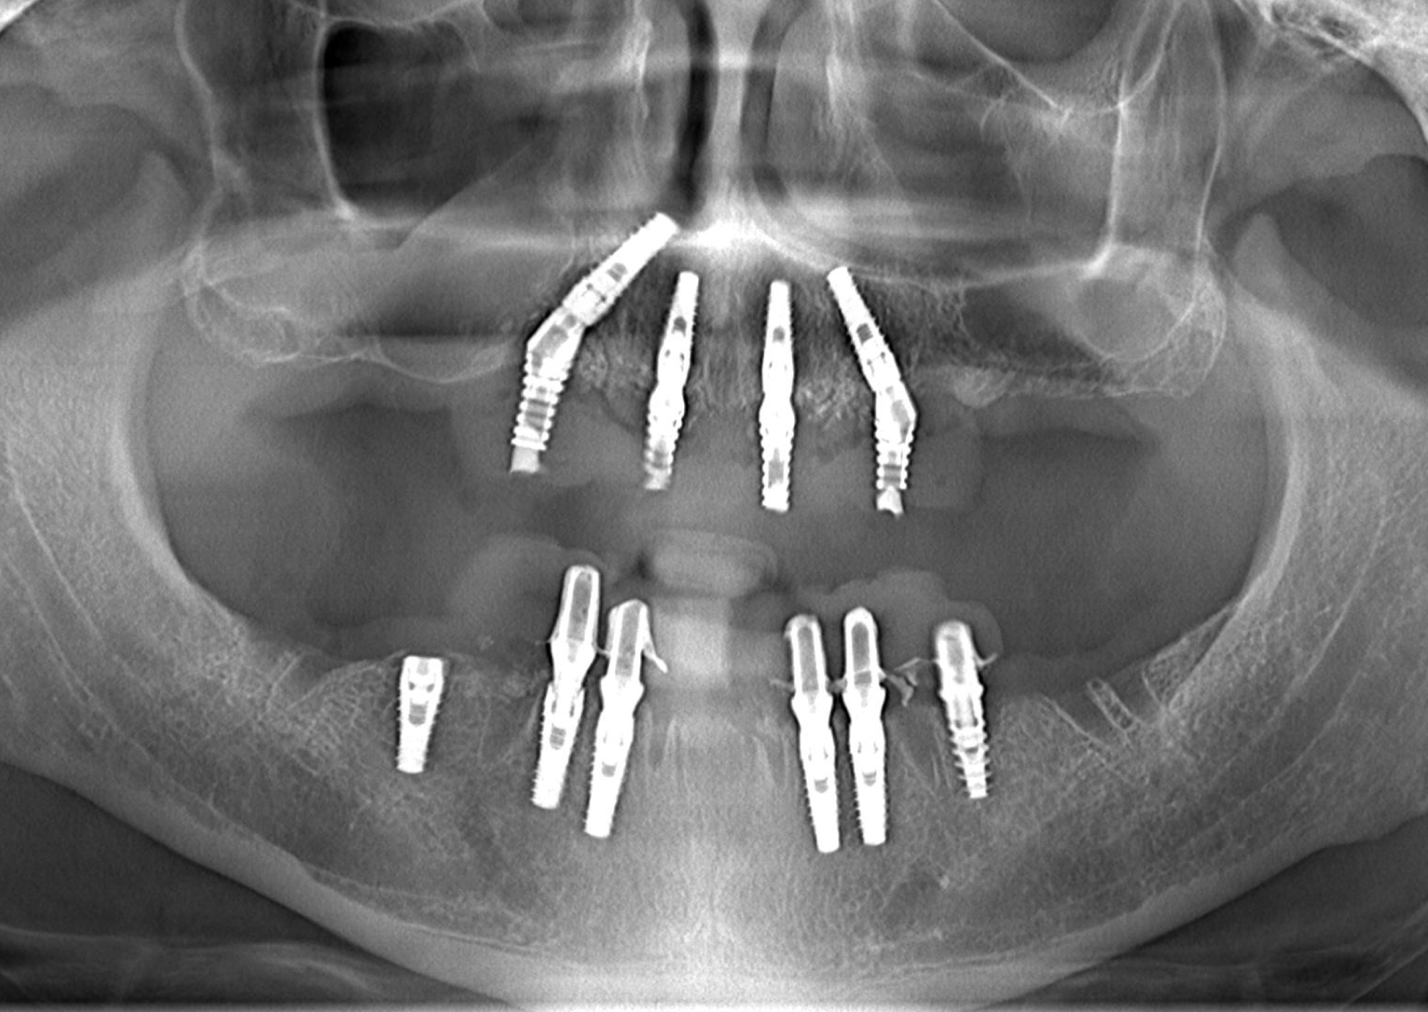

Sinus Avoidance Technique: Placement of 4 Upper Jaw and 6 Lower Jaw Implants

Case Presentation: A patient presented with significant bone resorption in both the upper and lower jaws, necessitating implant-supported prosthetic rehabilitation. However, due to patient preference or anatomical considerations, sinus augmentation was not pursued in the upper jaw. Instead, a sinus avoidance technique was employed to place 4 implants in the upper jaw, while 6 implants were placed in the lower jaw, with temporary prosthetic loading within 72 hours.

Treatment Implementation: Implant placement was meticulously planned in both the upper and lower jaws to maximize bone anchorage and ensure optimal support and stability for the future prostheses. The chosen implants were strategically positioned to avoid the sinus cavities in the upper jaw while achieving ideal placement in the lower jaw. Naxis implants were selected for their reliability and compatibility with the sinus avoidance technique. Temporary prostheses were loaded onto the implants within 72 hours post-surgery to provide immediate function and esthetics.

Outcome: The utilization of the sinus avoidance technique resulted in successful implant placement in both the upper and lower jaws, providing stable foundations for prosthetic restoration. Despite the absence of sinus augmentation in the upper jaw, the patient experienced no complications, and all implants exhibited favorable osseointegration.